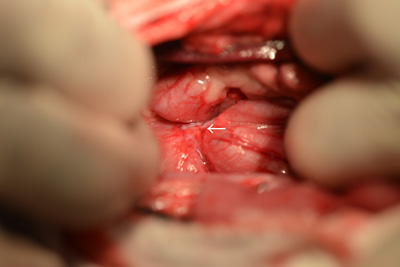

当院での症例のご紹介 みなみ野動物病院 八王子みなみ野。

Case50 試験開腹で反応性肉芽組織と診断された腹腔内腫瘤の犬の1例 –つつじヶ丘動物病院東京都調布市の動物総合病院。一般診療、循環器科、腫瘍科など。

Case50 試験開腹で反応性肉芽組織と診断された腹腔内腫瘤の犬の1例 –つつじヶ丘動物病院東京都調布市の動物総合病院。一般診療、循環器科、腫瘍科など。